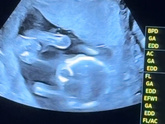

Сходили сегодня на УЗИ, срок 16 недель и 5 дней по УЗИ. Заскринила вроде попик, Как думаете кто у нас? Я не понимаю, но как будто мальчик ??